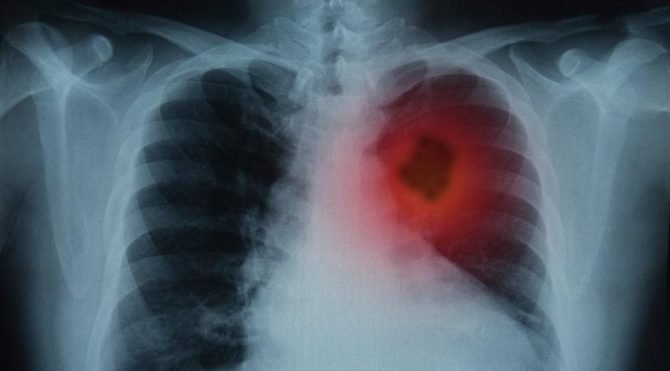

ABD'de elektronik sigara nedeniyle "ağır akciğer yanması" teşhisi koyulan çocuğa, çift taraflı akciğer nakli yapıldı. LiveScience'ın haberine ......

The Center for Disease Control ( CDC ) kurumunun yaptığı açıklamalarına göre elektronik sigara tüketimi ile ilişkili akciğer ......

Ülkede 24 eyalette elektronik sigaraların neden olduğu tahmin edilen akciğer hastalığından ölenlerin sayısı ise 34’ten 37’ye yükseldi.BELİRTİLERİ ......